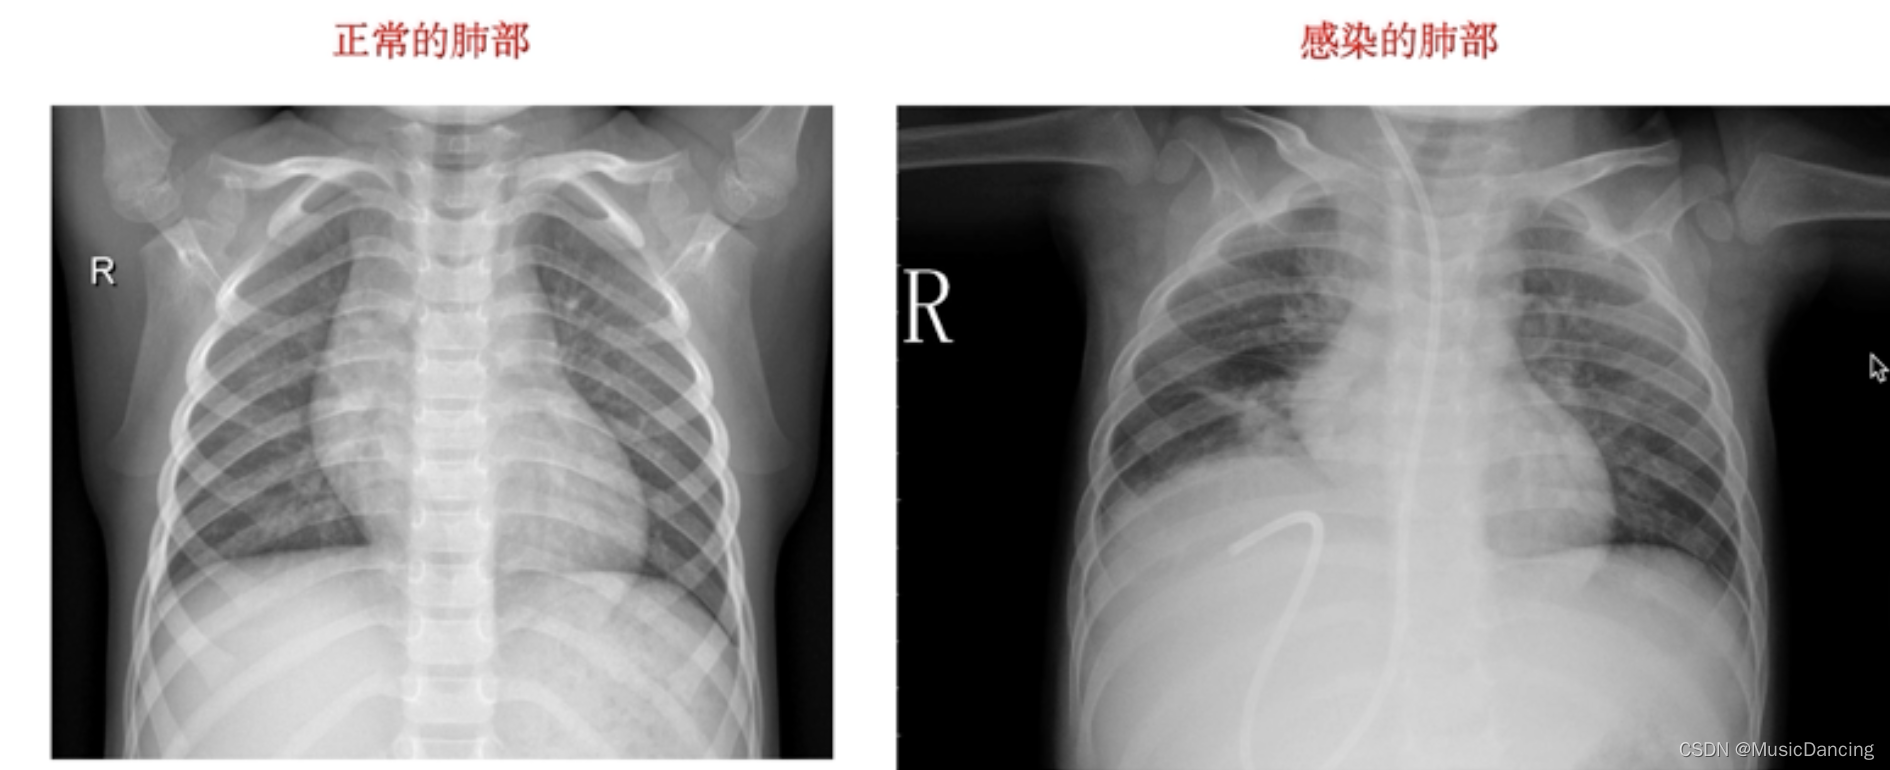

样本展示: